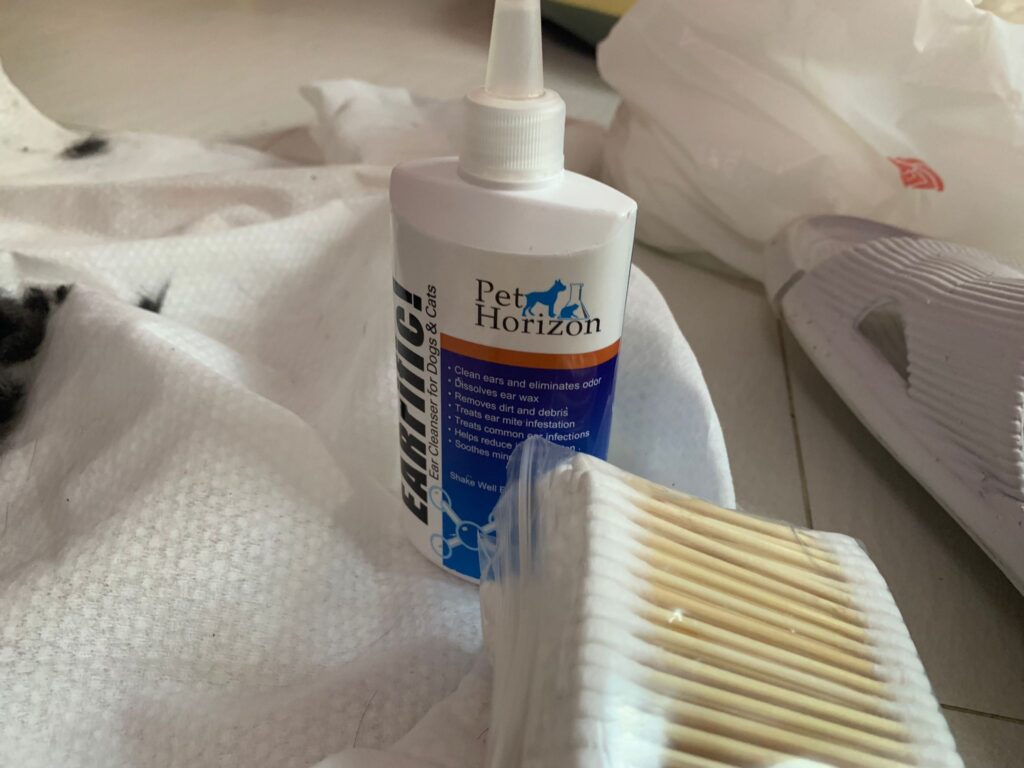

Morning: cut nails and clean ears

11am+: Cut nails, clean ears.

Morning: super cute. Thru out queuing for grooming. I let him cut nails and clean ears. Just now send out his poo for checking 4.75/10.

Noon: cut nails and clear ears – nails long and ears dirty. he is the first to q up.

Taking full bloods, urine n serum n Afast see spleen for any changes. Nails cutting n ear cleaning.

11Am: 3.8kg – drop 170g. Cut nails and clean ears, dirty. Also shower, struggle a lot, scare of water la. Hair dryer he is ok, loud and hot also ok

Morning: brush him and clean both ears. Seem